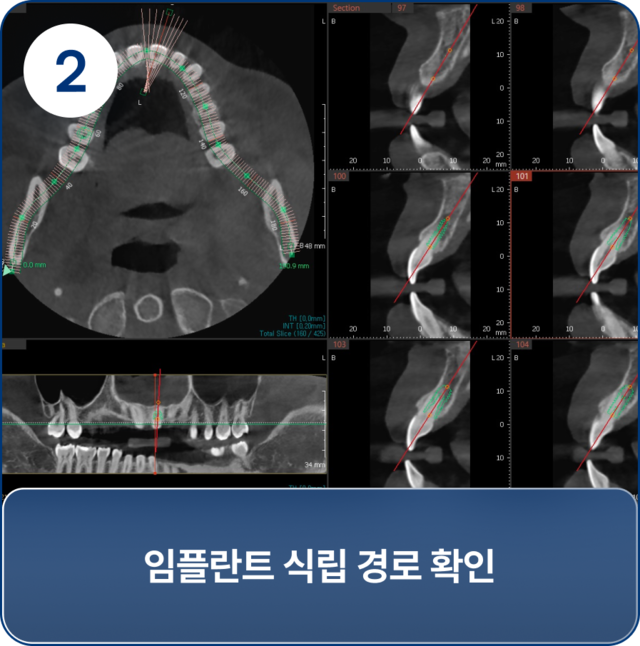

정확한 3D CT를 통해

성공적인 치료 계획을 세우고

좋은 결과를 확인하세요.

임플란트는 구강 구조를 상세하게 파악해야

성공적인 치료 계획을 세울 수 있습니다.

연세이타임치과는 3D CT를 사용하며,통증을 최소화하고 좋은 결과

이끌어 냅니다.